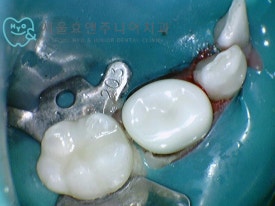

맞는 사이즈의 크라운 접착 후 모습입니다. 역시 유치 지르코니아크라운은 예뻐요^^

엑스레이에서 확인해보면 가운데 치아는 신경치료하지 않은 치아임을 알 수 있고, 크라운이 뜨거나 하지 않고 정확히 잘 들어갔음을 알수 있습니다. 크라운의 양쪽 치아도 눈으로봐서는 치료한 치아인지 알 수 없을 정도로 깔끔하게 레진으로 잘 치료되었습니다.

맞는 사이즈의 크라운 접착 후 모습입니다. 역시 유치 지르코니아크라운은 예뻐요^^엑스레이에서 확인해보면 가운데 치아는 신경치료하지 않은 치아임을 알 수 있고, 크라운이 뜨거나 하지 않고 정확히 잘 들어갔음을 알수 있습니다. 크라운의 양쪽 치아도 눈으로봐서는 치료한 치아인지 알 수 없을 정도로 깔끔하게 레진으로 잘 치료되었습니다.